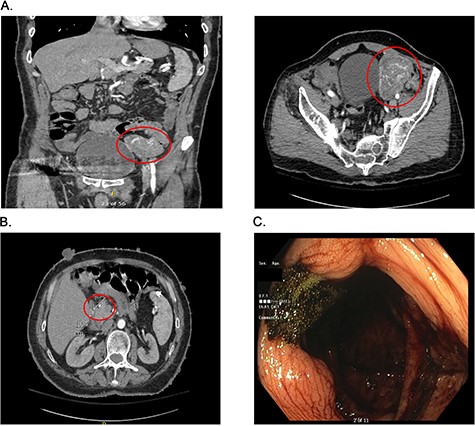

Presurgical diagnostics. (A) CT imaging of the large jejunal mass. (B) CT imaging of small duodenal mass. (C) Blood at the ileo-cecal valve.

On admission at the outside hospital, the patient’s hemoglobin was 6.6 g/dl, with normal platelets, partial thromboplastin time and prothrombin time. Diagnostic workup at the outside institution included a nuclear medicine gastrointestinal scan (mTc-labeled RBCs), which was negative for abnormal bleeding. On hospital Day 2, his hemoglobin failed to respond appropriately to transfusions and a computed tomography angiogram (CTA) was completed, which showed a 6.9 × 5.8 × 6.8 cm hyper-vascular mass in the left pelvis; abutting the left border of the bladder medially, iliac arteries and veins posteriorly, rectus sheath anteriorly and the small and large bowel (Fig. 1A). Vascular supply of the mass was identified to originate from branches of the superior mesenteric artery (SMA) and appeared to be contiguous with the adjacent jejunum. The mass was noted to also abut, but not involve, the sigmoid colon. The CT scan further noted a 9 mm enhancing tumor in the second portion of the duodenum anteriorly (Fig. 1B). After administration of five total units of packed red blood cells with limited improvement in hemoglobin, the patient was transferred to our institutions for further management.

The patient arrived hemodynamically stable and underwent esophagogastroduodenoscopy (EGD). The EGD was unremarkable with no visualization of the previously mentioned duodenal mass. Colonoscopy was performed, which was notable for bright red blood present throughout the entire colon as well as blood 5 cm proximal to the ileocecal valve (Fig. 1C). As the patient continued to have bloody output per rectum, with insufficient response to transfusion, interventional radiology was consulted and proceeded with mesenteric angiography with intervention (Fig. 2A). The hyper-vascular mass was found to be supplied by ileal branches of the SMA, which were successfully embolized (Fig. 2B and C). After conversations with the interventional radiology team and the patient, the decision was made to proceed with an exploratory laparotomy and resection of the identified mass.